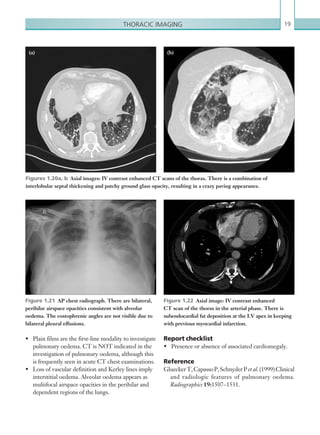

Figures 1.20a, b  Axial images: IV contrast enhanced CT scans of the thorax. There is a combination of

interlobular septal thickening and patchy ground glass opacity, resulting in a crazy paving appearance.

GlueckerT,CapassoP,SchnyderPet al.(1999)Clinical

and radiologic features of pulmonary oedema.

Radiographics 19:1507–1531.

•	 Plain films are the first-line modality to investigate

pulmonary oedema. CT is NOT indicated in the

investigation of pulmonary oedema, although this

is frequently seen in acute CT chest examinations.

•	 Loss of vascular definition and Kerley lines imply

interstitial oedema. Alveolar oedema appears as

multifocal airspace opacities in the perihilar and

dependent regions of the lungs.

Key points

•	 Pulmonary oedema is a medical emergency and

can cause rapid-onset respiratory failure.

•	 The commonest cause of pulmonary oedema is

pulmonary venous hypertension secondary to left

ventricular failure, although other causes include

fluid overload and ARDS. In the absence of

associated cardiomegaly, non-cardiogenic causes

should be considered.

interstitium (resulting in smooth interlobular septal

19Thoracic imaging

Report checklist

•	 Presence or absence of associated cardiomegaly.

Reference